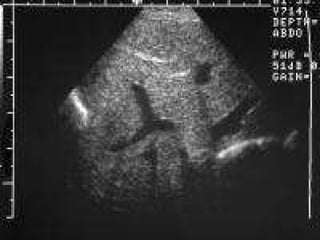

INV:   X ray chest: bowel loops in the chest Mediastinal shift with Ryles tube in situ showing the tip. X ray abdomen : Abdomen-relatively devoid of gas. Prenatal sonography : Bowel loops in the chest. CT& MRI : Defect in the diaphragm compressed fetal lung intestinal loops in the thorax. ABG : pH:7.2 paCO 2 >40mmHg paO 2 >60mmHg CONGENITAL DIAPHRAGMATIC HERNIA